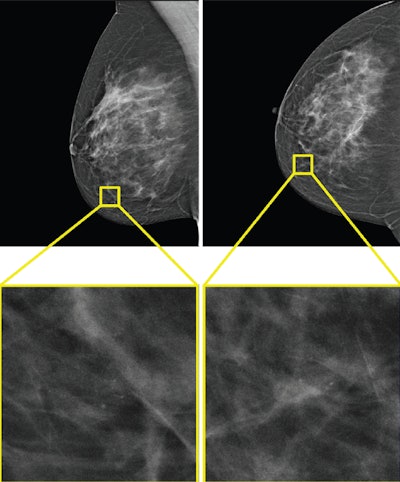

The only example of a screening exam with a screen-detected cancer that would have been missed by AI in a hybrid reading strategy based on the AI uncertainty score of the entropy of the mean probability of malignancy (PoM) score of the most suspicious region. During screening, a 52-year-old woman was recalled following arbitration scoring of the right breast as Breast Imaging Reporting and Data System (BI-RADS) 4 after the first and second radiologists scored the right breast as BI-RADS 1 and 4, respectively. This woman would not have been recalled if the examination was read by the AI model, which assigned a PoM score of 30, which would be classified as a certain prediction with an uncertainty quantification of 0.57. Both the mediolateral oblique (left) and craniocaudal (right) views of the affected breast are shown. The boxes indicate the calcifications found during screening, and the final diagnosis of this examination was ductal carcinoma in situ.RSNA